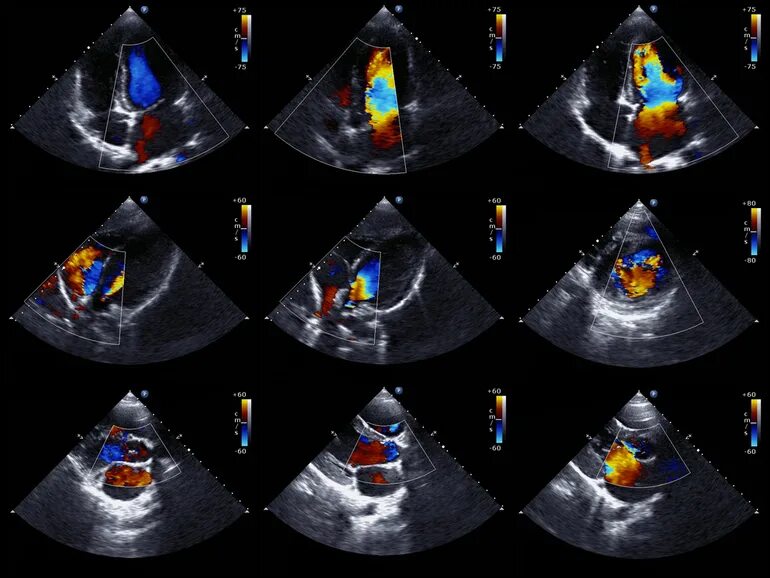

Эх сердца